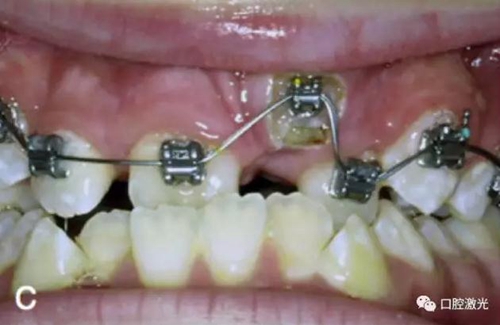

治療前

激光牙齦切割后即刻

粘接托槽

3周后效果